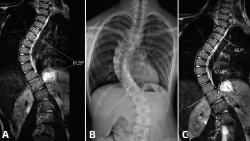

Cualquiera de los sistemas tecnológicos de TC en bipedestación ronda los 300.000 dólares(11). Ello dista de ser asumible por la mayoría de los servicios de traumatología y ortopedia en la actualidad, habida cuenta de que solo se utiliza para el estudio de la articulación del tobillo y el pie. Los estudios de TC en carga axial simulada pueden ser válidos, sin un sobrecoste añadido. Además, estos dispositivos pueden emplearse para el estudio de otras regiones anatómicas. Dado que está fabricado completamente en metacrilato, ha sido utilizado en nuestro hospital para estudios de RM de la cadera o columna con carga simulada (Figura 9)(22).

Figura 9. Resonancia magnética (RM) convencional en supino de columna completa en paciente con escoliosis (A); telerradiografía en bipedestación de columna completa (B); y RM en carga simulada del mismo paciente (C). Nótese el aumento del ángulo Cobb evidenciado en RM con carga simulada que se correlacionó con la radiografía en bipedestación.

Por otro lado, aunque aparentemente la posición erguida podría representar más fielmente la carga fisiológica, estudios recientes de carga simulada abogan por esta metodología demostrando su validez y reproducibilidad con cargas axiales de al menos un 70% del peso corporal del paciente(23). Otra de las ventajas que detectamos mediante dispositivos de carga simulada es que el paciente está lo suficientemente relajado para permitir el movimiento del pie y el tobillo en el plano del espacio que precise estudiarse y mantener esta posición durante la prueba(24). Esto último se torna más difícil en la posición erguida.